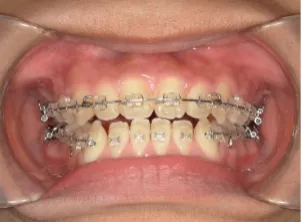

治療中④中2:マルチブラケット法へ移行:上下正中を合わせたい

*マルチブラケット法